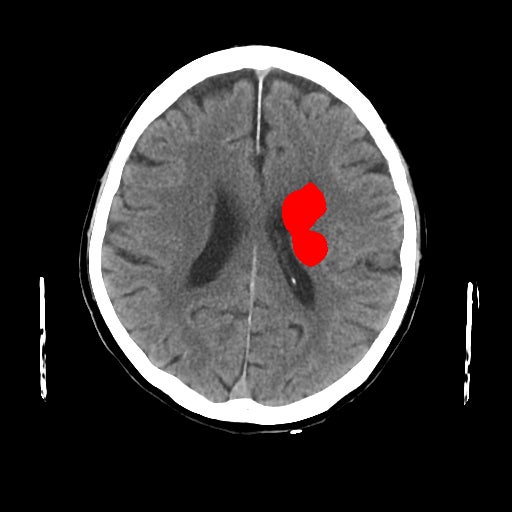

1-1. 高吸収領域の検出・表示例(下)

頭部CT検査において、周囲に比べ白く映る部分(高吸収領域)が見られる場合には、脳出血が疑われます。脳出血は高血圧・脳腫瘍・脳血管の異常などが要因となり、脳の動脈が破れて脳内部に出血した状態を指します。一方、周囲に比べ黒く映る部分(低吸収領域)が見られる場合には、脳梗塞が疑われます。脳梗塞は、脳内の血管が詰まるなどにより血液の流入が止まり、脳に酸素や栄養が行き渡らなくなる状態です。また、急性期の脳梗塞では、頭部CT検査において、灰白質と白質の境界が消失するなどの所見(ECS=early CT sign)が見られ(2)、こうした所見を見落とさずに治療につなげることが肝要です。